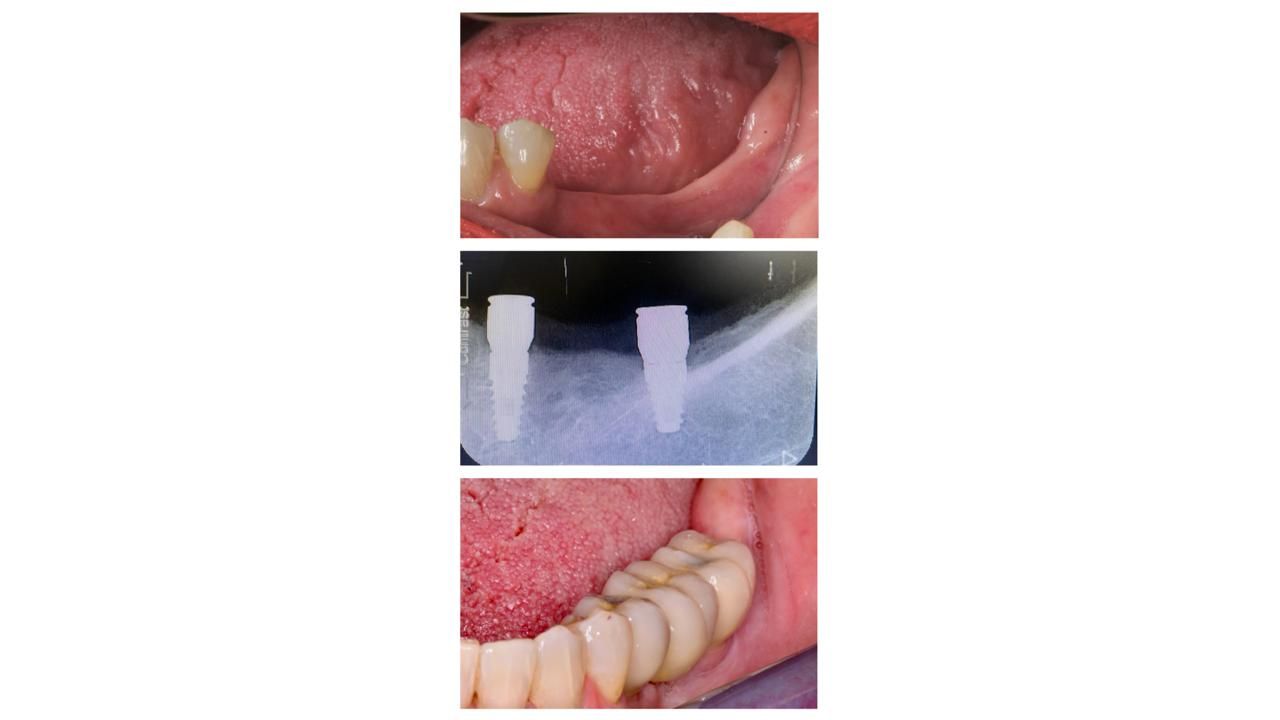

Diseño de sonrisa

Armonización estética con enfoque funcional.